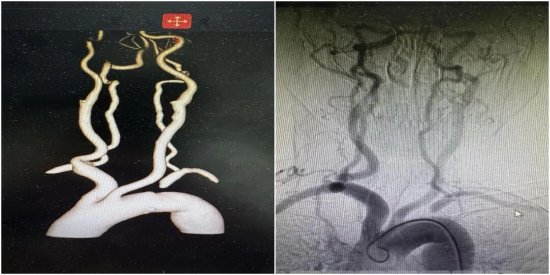

入院后,进行了头颈部CTA及全脑血管造影术(DSA),进一步证实了判断——张女士左侧锁骨下动脉起始段完全闭塞。正是这根血管的堵塞,导致血液无法顺利流向左侧上肢和脑部后循环,反而通过左侧椎动脉从大脑里“偷”血,从而引发了严重的头晕和上肢缺血症状。

所谓“会师技术”,就像是在山体隧道挖掘中,从山的两端同时动工,在中间汇合。一方面,继续保留股动脉通路,从近心端进行“正向”试探;另一方面,在张女士左侧手腕处开辟第二条微创通道(桡动脉入路),从血管远端进行“逆向”进攻。能否在原本搏动微弱的桡动脉上穿刺成功是逆向通路建立成功的关键。在神经内科介入团队的努力下,成功穿刺左侧桡动脉,在DSA高清影像的引导下,逆向导丝犹如长了眼睛一般,缓慢且坚定地向前推进。终于,在反复调整角度和路径后,两根导丝在闭塞段内精准“会师”。随后,利用逆向导丝作为“生命线”,将正向球囊顺利送至病变部位,依次进行扩张。随着一枚支架精准释放在左锁骨下动脉开口处,血管瞬间被撑开。

术后即刻造影显示:闭塞的血管重新开通,血流畅通无阻,左侧椎动脉恢复了正向供血。原本摸不到的左侧脉搏、乃至远侧桡动脉也恢复了有力跳动。

(支架顺利植入左锁骨下动脉开口处,造影提示左侧椎动脉正向血流恢复)